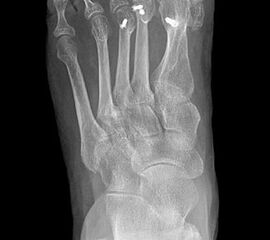

Klinisches Erscheinungsbild eines Hallux varus (eigenes Bildmaterial)

Abbildung 1